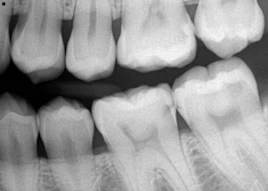

Goldberg: Unlike other caries detection systems, the Ortek ECD measures the conductivity of enamel. The ECD was specifically designed to help dental professionals diagnose and monitor early cavitated lesions in the pits and fissures located on the occlusal surfaces of posterior teeth. If the dentin-enamel junction is breached by demineralization, hydrostatic pressure that exists within dentinal tubules will allow minuscule amounts of conductive dentinal fluid to enter the breached enamel site, allowing the ECD to complete an electrical circuit.

Loss of mineral from enamel as a result of caries activity increases porous size and enamel porosity. As this demineralization increases, more dentinal fluid enters the breached site. The more fluid detected results in a higher current and an increasing digital caries score that is digitally displayed from 01–100. Intact tooth enamel is a good insulator and is electrically nonconductive. When the enamel at the bottom of a pit or fissure is intact, the circuit path is opened and no current can flow, indicating no cavitated lesion and a zero score.